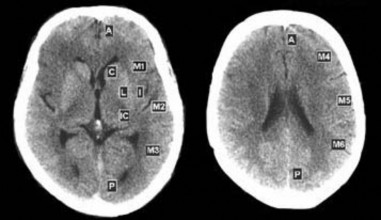

- Tổn thương não trên CT scan đánh giá bằng thang điểm ASPECTS. Thang điểm ASPECTS chấm điểm dựa trên đánh giá tổn thương thiếu máu não tại vùng tưới máu của động mạch não giữa [37]. Vùng tưới máu của động mạch não giữa được chia làm 10 vùng (hình 2.1) trên lát cắt ngang qua các nhân nền

và lát cắng ngay sát phía trên các nhân nền, gồm bốn vùng sâu: I (insular – thùy đảo), C (caudate – nhân đuôi), IC (internal capsule – bao trong), L (lenticular – nhân đậu) và sáu vùng nông: M1, M2, M3 ở lát cắt qua các nhân nền, và M4, M5, M6 ở lát cắt sát trên các nhân nền. Nếu không có tổn thương, điểm số sẽ là 10, cứ mỗi vùng bị tổn thương nhồi máu não sẽ bị trừ một điểm, đến nặng nhất là 0 điểm khi tổn thương toàn bộ vùng tưới máu động mạch não giữa. Thang điểm ASPECTS đã được chứng minh có độ tương hợp cao giữa các người đánh giá và có độ tin cậy cao trong tiên lượng bệnh [37], [107]

Hình 2.1. Các phân vùng chấm điểm ASPECTS “Nguồn: Pexman JHW, 2001” [107]